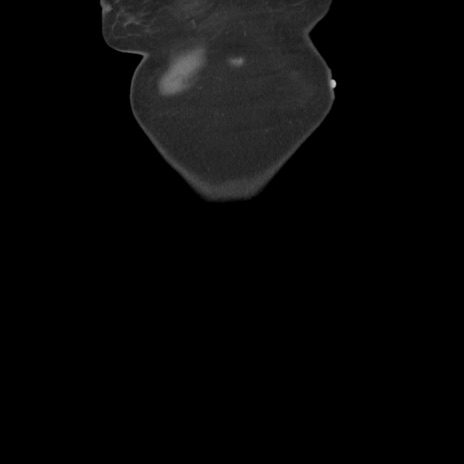

横断像

【症例】80歳代女性

【主訴】下腹部痛

【現病歴】約8時間前より下腹部痛の出現あり、救急外来受診。

【既往歴】両側付属器切除

【身体所見】意識清明、下腹部正中に手術痕あり、その部位に一致して圧痛と反跳痛あり。腸蠕動音は亢進。

【データ】WBC 9300、CRP 0.15